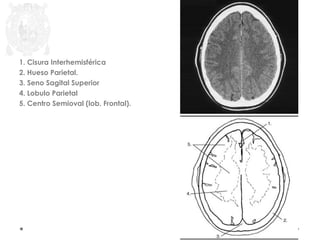

1. Cisura Interhemisférica

2. Hueso Parietal.

3. Seno Sagital Superior

4. Lobulo Parietal

5. Centro Semioval (lob. Frontal).